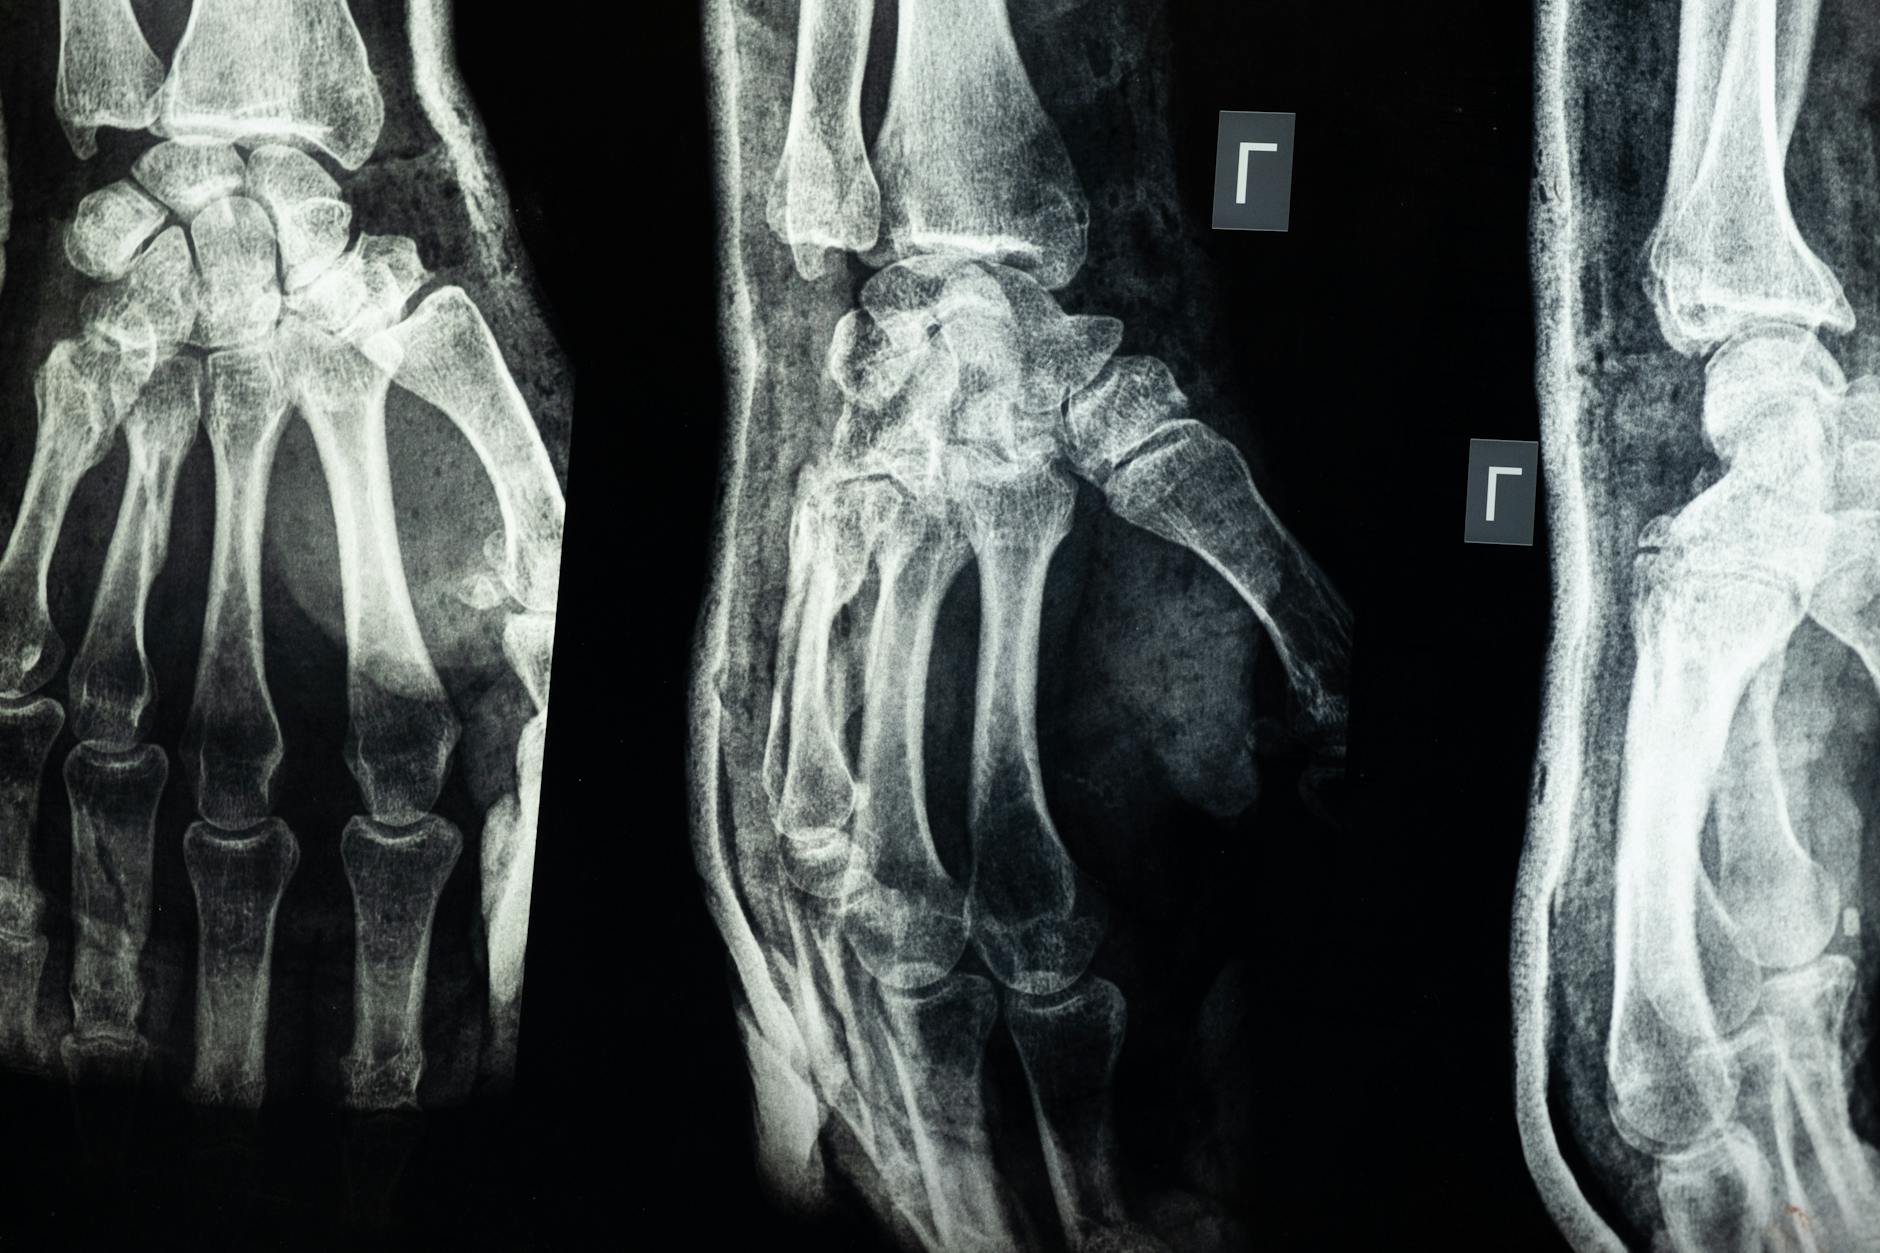

Falls are the leading cause of traumatic pelvic fractures in people over 65, and people with dementia fall at roughly twice the rate of cognitively intact older adults. The fractures that result are often different from those seen in younger patients. Rather than the high-energy ring disruptions caused by car accidents, elderly patients typically sustain insufficiency fractures — breaks through bone that has already been weakened by osteoporosis. These fractures may involve the pubic rami, the sacrum, or both, and they frequently go undiagnosed initially because they do not always appear on standard X-rays. CT scans or MRI are often needed to confirm the injury.

A specific and common example involves sacral insufficiency fractures, which account for an estimated 1 to 5 percent of all fragility fractures but are missed on initial imaging in up to 60 percent of cases. The patient presents with vague low back or buttock pain, the X-ray looks unremarkable, and the pain gets attributed to muscle strain or arthritis. In a dementia patient who cannot clearly describe where the pain is or how it started, weeks can pass before the fracture is identified — if it is identified at all. Even when pelvic fractures heal, the resulting scar tissue and subtle changes in alignment can leave permanent instability. The pelvis may bear weight asymmetrically, altering gait mechanics and placing abnormal stress on the hip joints, lumbar spine, and the opposite side of the pelvis. For someone already navigating the cognitive challenges of dementia, this physical asymmetry adds another layer of fall risk that compounds over time.